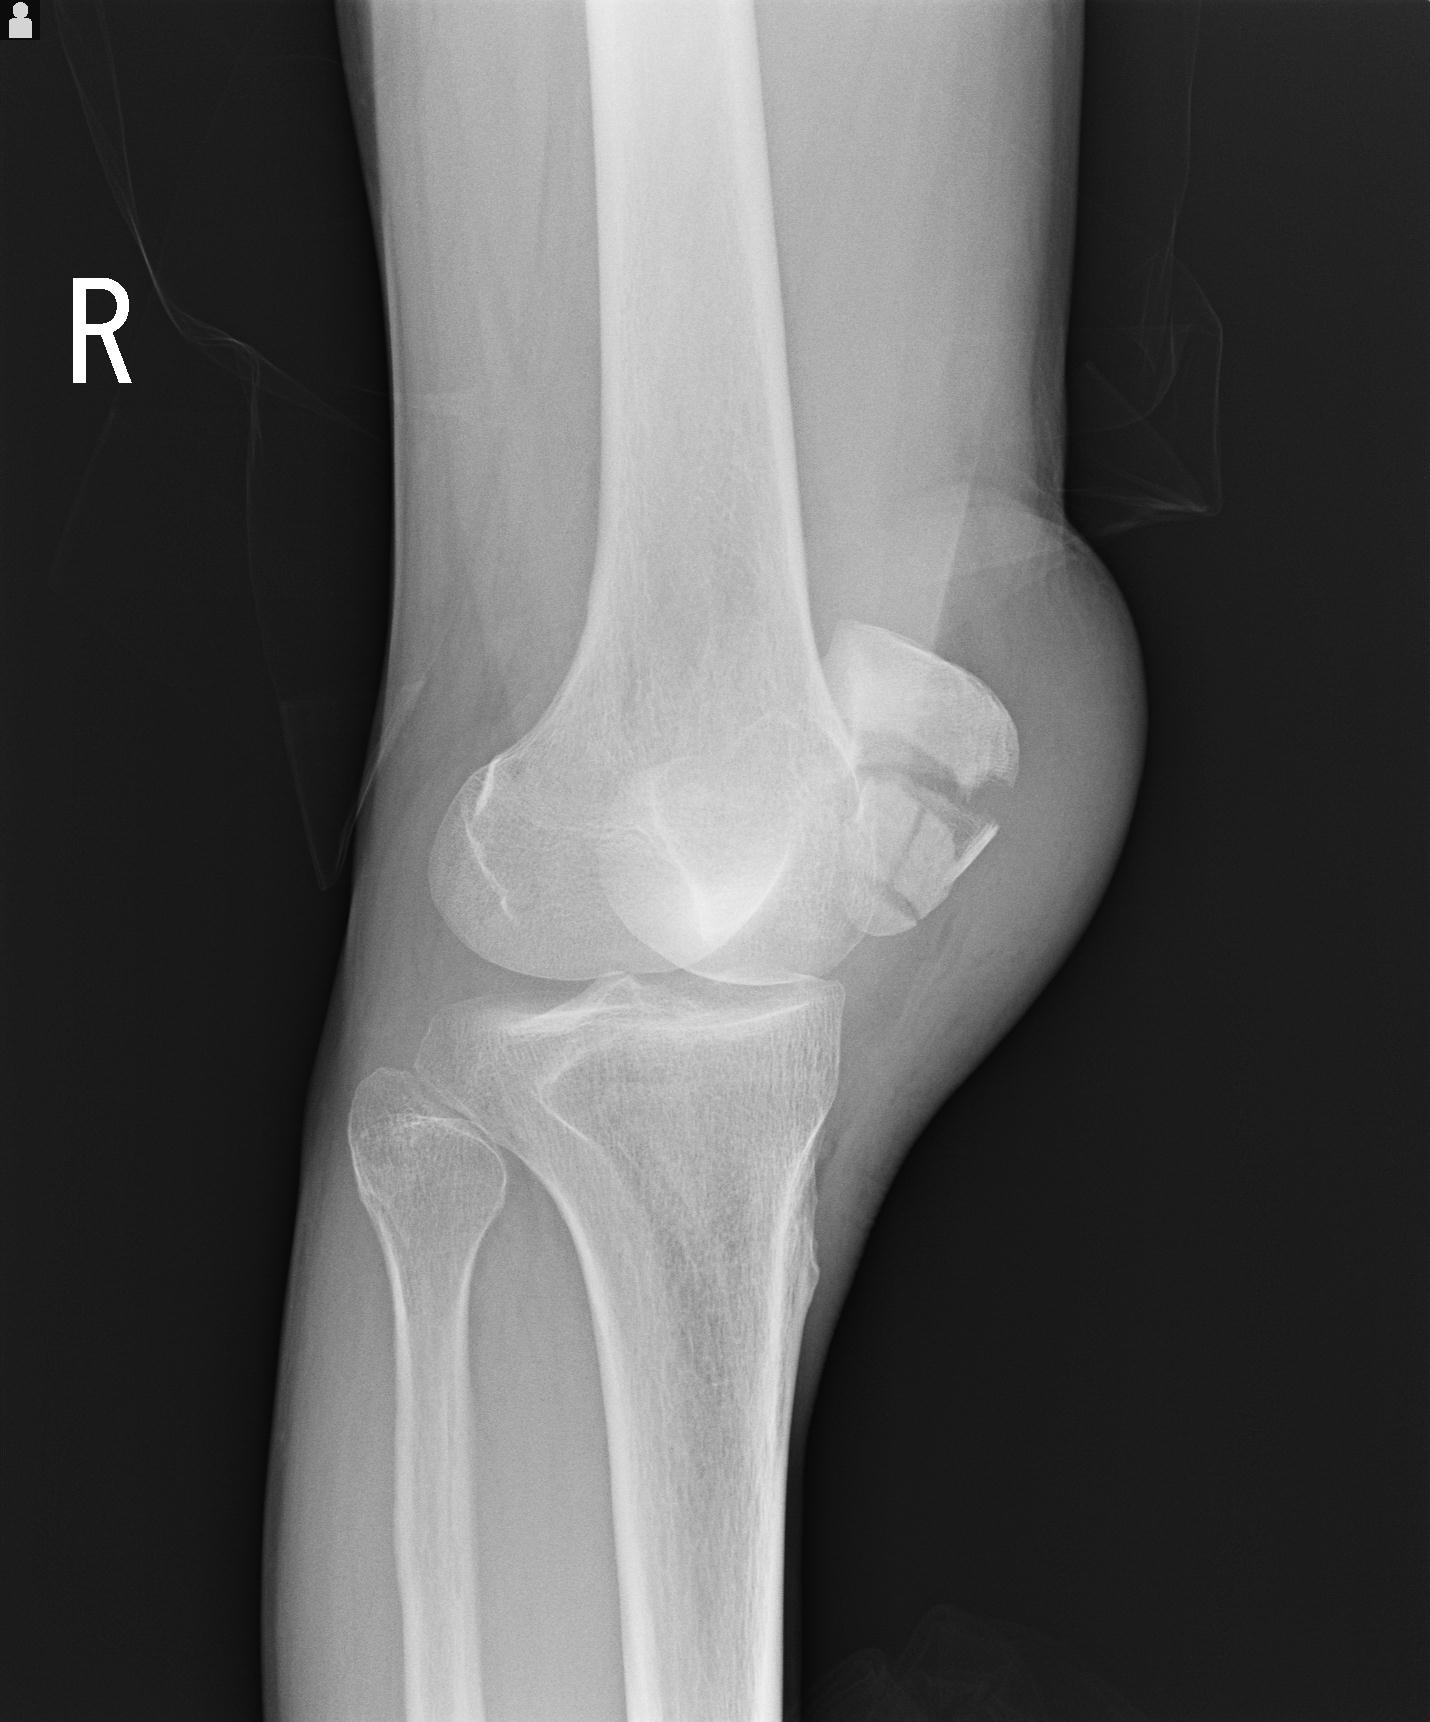

2271 1/25 右肘 4R 1/27 4R 3/24 4R 94歳女性 右通顆骨折